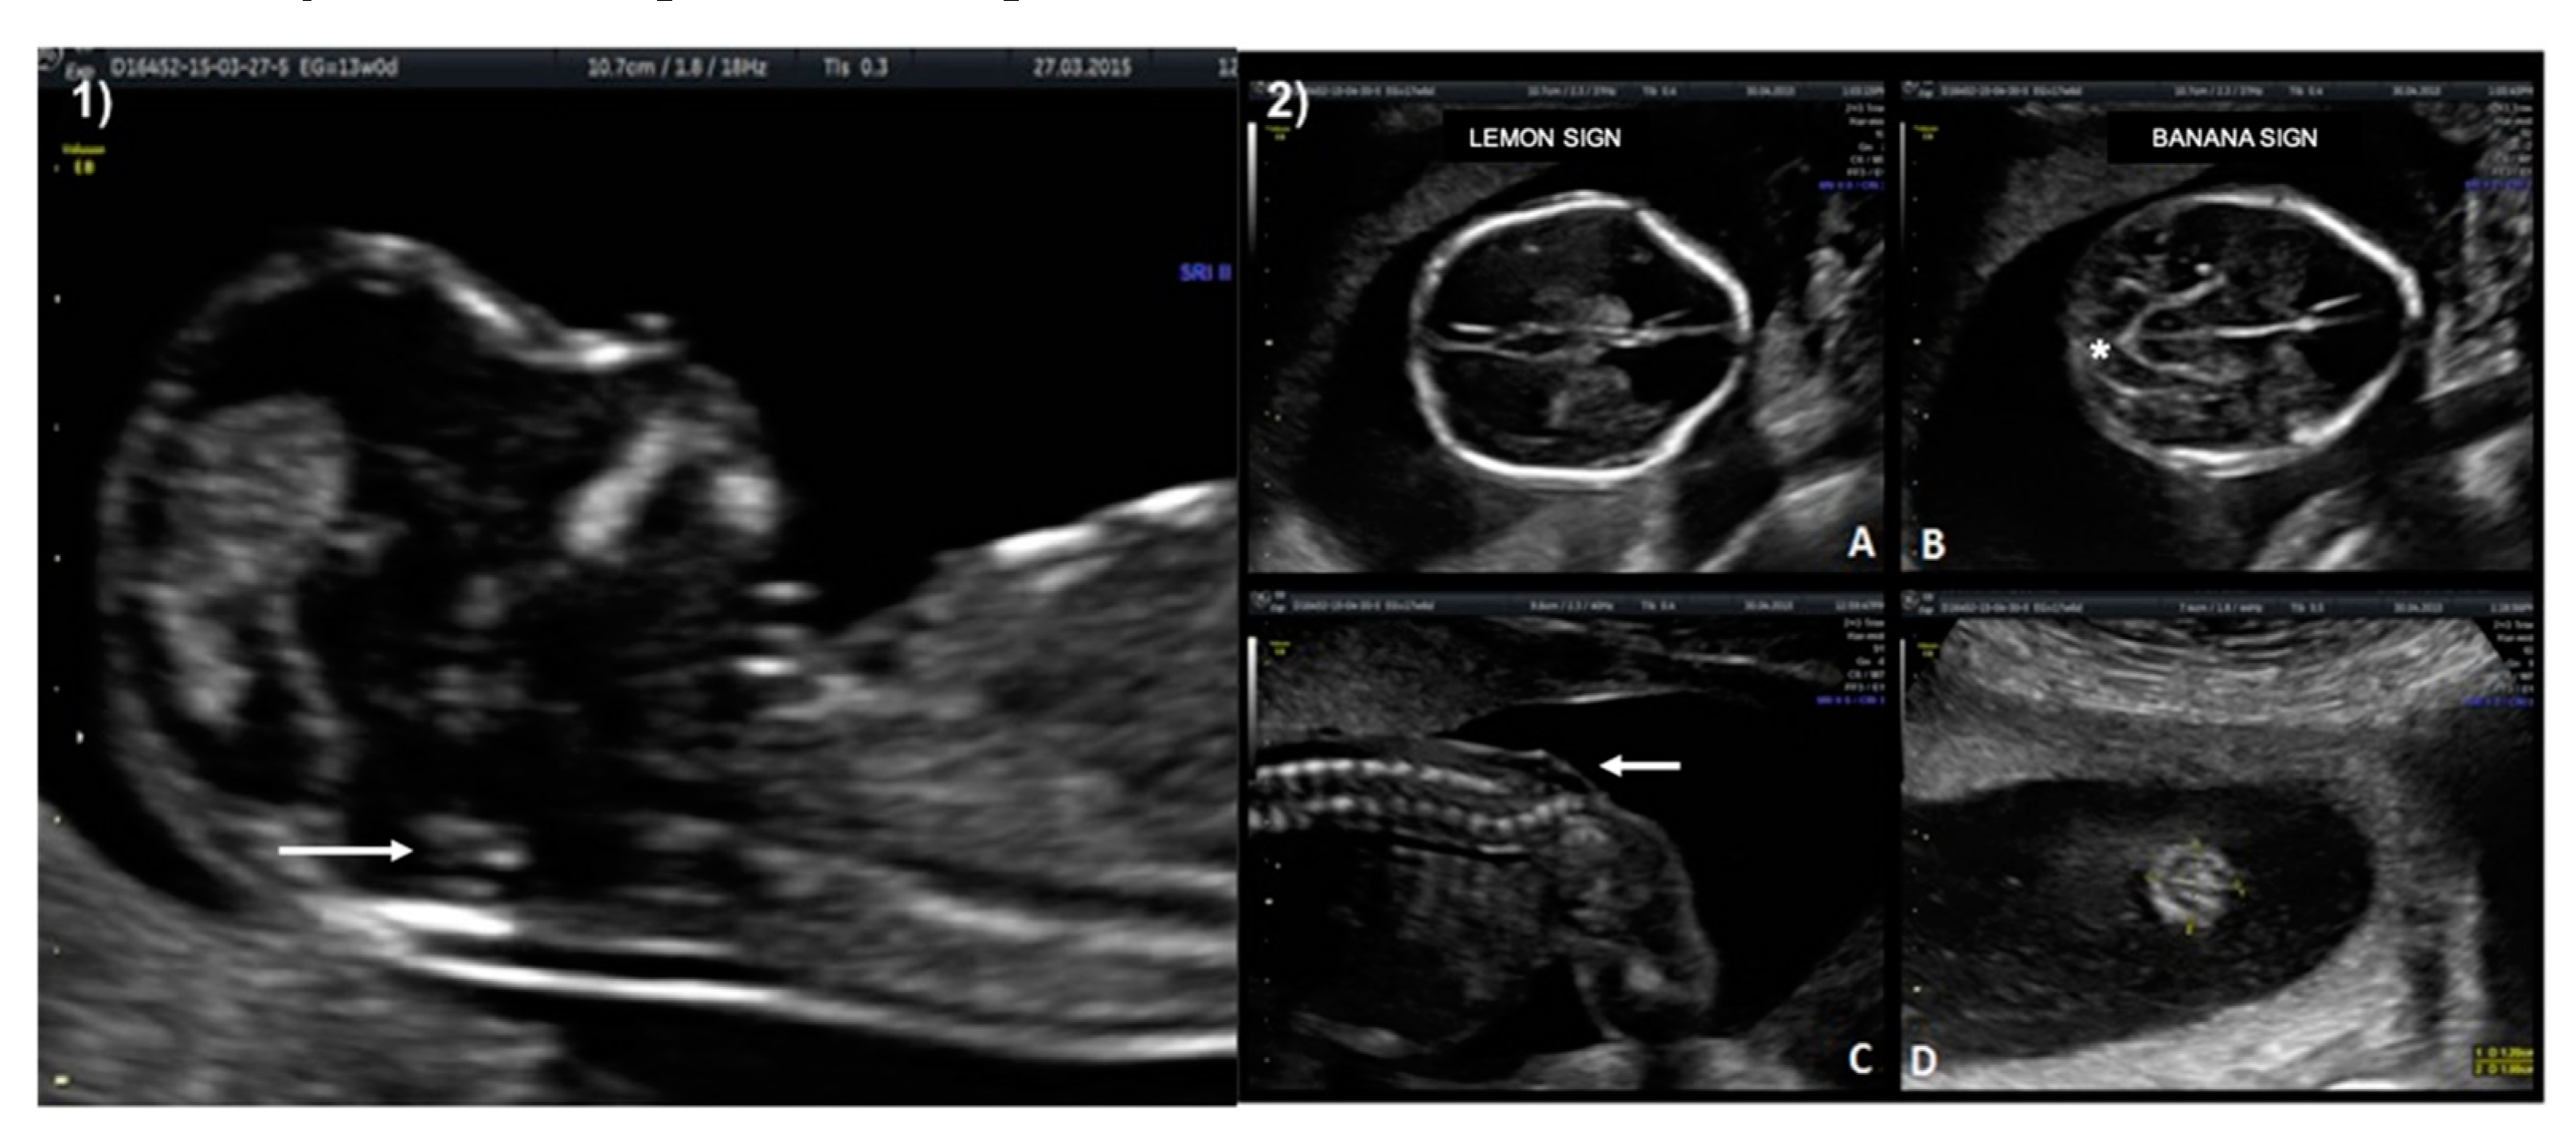

A 33-year-old patient G3 P2 without relevant clinical history was referred for routine first-trimester screening at 13 weeks of gestation. The fetus′s CRL was 63 mm, NT measured 1.5 mm, nasal bone was present, and IT was absent (Figure 3-1). A follow-up US scan was performed at 19.4 weeks of gestation. Both the “lemon” and “banana” signs were present (Figure 3-2.A,2.B), and the diagnosis was confirmed by observing an open defect between L5–S1 (Figure 3-2.C). After counseling, the patient opted for expectant management and postnatal repair.

Figure 3. Case 2. First-trimester scan: (1) Ultrasound image in the mid-sagittal plane of the fetal face in a case of spina bifida aperta demonstrating compression of the fourth ventricle with no visible IT (white arrow). Second-trimester scan: (2.A) Lemon sign on axial plane at 19 weeks. (2.B) Banana sign in second-trimester scan (*), (2.C) Sagittal plane of the spine shows the neural tube defect between L5-S1 (white arrow). (2.D) Axial image from the sac.